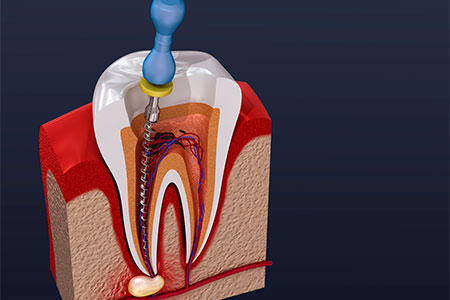

O tratamento endodôntico, popularmente conhecido como “tratamento de canal”, é um dos procedimentos mais importantes e eficazes da odontologia moderna. Longe da fama do passado,